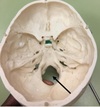

1. What is the name giving to this structure? 2. What structures are present in the lateral grooves of this structure?

1. Skull Cap or Calvaria 2. Middle Meningeal Vessels